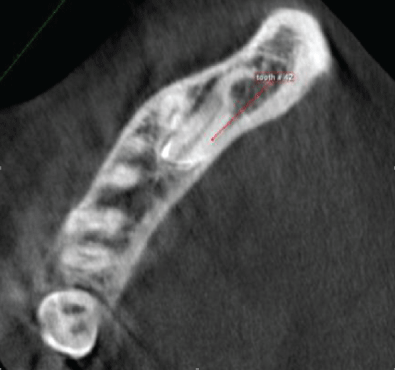

The right mandibular lateral incisor (#42) impacted lingual to impacted tooth # 43 and the crown is directed distally below the apices of first and second premolar , with this pathway of impaction it seems it will be difficult to exposes the tooth to be aligned in the proper location (Figures 4-6).

Figure 4: CBCT, sagittal view showing impacted right mandibular lateral incisor the crown directed distally.

Figure 6: CBCT, axial view showing impacted right mandibular lateral incisor in almost horizontal position at the level of root apices of adjacent teeth.